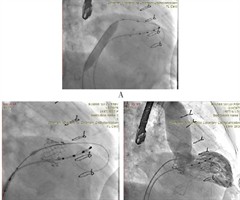

经导管二尖瓣“瓣中瓣”置换术治疗人工二尖瓣生物瓣衰败的安全性和有效性分析

摘要:自的评估经导管二尖瓣"瓣中瓣"置换术(ViV-TMVR)治疗人工二尖瓣生物瓣衰败的安全性和有效性。方法选取17例因二尖瓣生物瓣衰败需行ViV-TMVR的患者,收集患者的年龄、性别、体质量指数(BMI)、二尖瓣生物瓣...